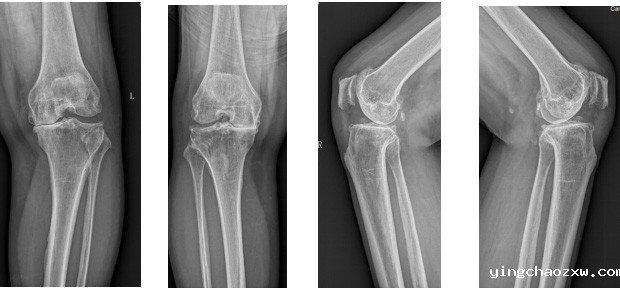

据悉,该患者为女性,现年55岁,双膝关节反复疼痛已有10余年,并伴有膝关节肿胀,膝关节屈曲活动受限,不能下蹲,上下楼非常困难。期间患者曾辗转多家外院进行治疗,均未见好转。患者入院后,骨伤科医疗团队完善相关检查,明确患者为双膝关节退行性病变。考虑到患者双膝关节炎病史较长,膝关节退变严重,膝关节已磨损软骨无法恢复,如继续采用保守治疗,效果并不理想,患者仍将长期忍受疼痛的折磨,严重影响生活质量。为了消除患者的痛苦,让患者早日恢复健康,骨伤科医疗团队综合研究患者病情,制定了科学、合理、安全、有效的治疗方案,于11月16日对患者实施了双膝内轴型人工关节置换术。术后患者膝关节疼痛消除,手术结束患者即可自行抬腿,屈伸膝关节,术后第二日无需持拐杖就可下床行走,手术获得圆满成功。

膝关节骨性关节炎是中老年人的一种常见关节疾病,它是由关节软骨磨损退化病变所致,给中老年人带来痛苦和磨难,甚至造成残疾。在我国,60岁以上的老年人有78.5%以上患有膝关节骨性关节炎。随着人口老龄化的不断加剧,膝关节退行性关节炎等疾病的发生率呈逐步上升趋势。数据显示,2022年国内全膝关节置换手术量预计达44.2万例。同时,有研究指出,近20%的患者对全膝关节置换的手术效果并不满意,其主要原因是术后膝关节出现不稳定情况。内轴型膝关节设计无需进行髁间截骨,通过手术医生对软组织的毫米级精准平衡,在极高的骨保留基础上提供更高的关节活动度以及更可靠的耐磨性能,尽可能地模仿自然膝关节的运动特征以重建膝关节正常的运动力学,维持膝关节在运动中的稳定性,使得术后的运动力学特征和患者步态更加自然,使患者术后感受更好,几乎“忘记”换过膝关节,进一步提高了患者的满意度。临床随访17年的结果显示内轴型膝关节具有极高的假体存留率(98.8%)和患者满意度(95%)。